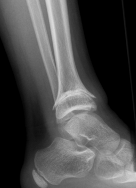

| SH I distal tibia / fibula | SH II distal tibia | SH III medial malleolus |

| Low risk growth arrest | 40% risk growth arrest | 30% risk physeal bar |